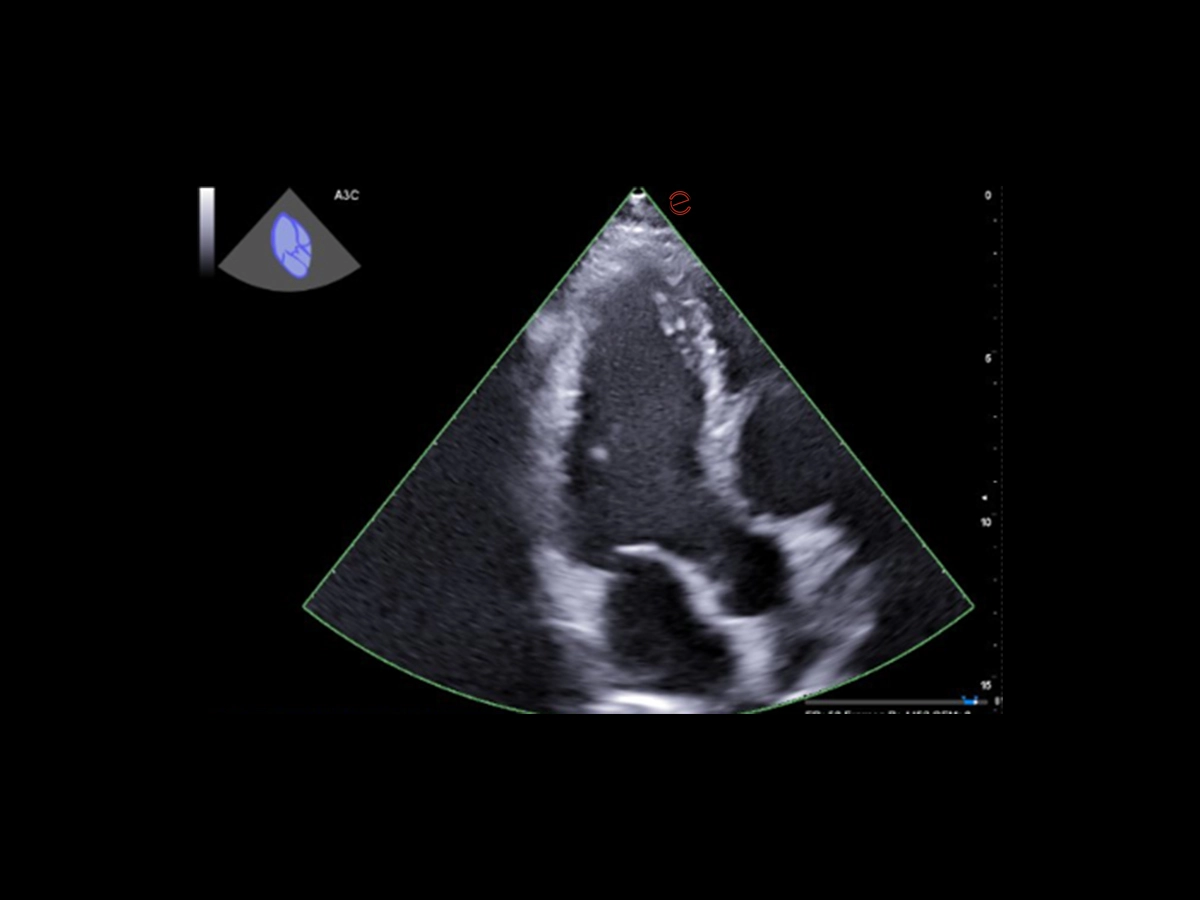

Intelligent workflow guidance with HeartScan Assistant

Esaote’s HeartScan Assistant supports clinicians during echocardiographic exams by automatically recognizing the scanning plane and displaying it on the screen. The ultrasound sector is highlighted with a colorcoded overlay that indicates the confidence level of the recognition, providing immediate visual feedback. This intelligent, AI-based feature is therefore designed to support operators in image acquisition during routine practice.